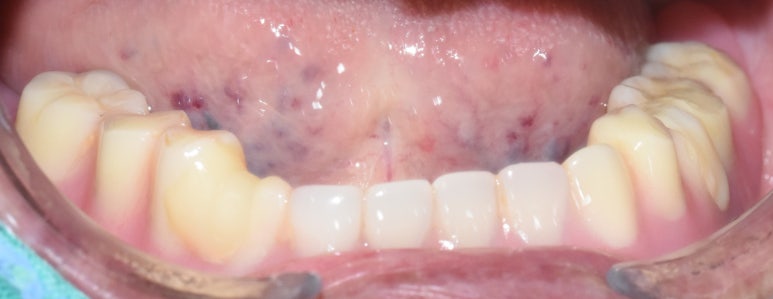

7.아래쪽 임플란트 최소 2개 심고 틀니 연결하여

덜 움직이는 틀니

8.다른 치과에서 한 아래틀니가 너무 아픈 환자분

아래 2개 임플란트를 심고 임플란트 틀니로 변경

아래치아 하나도 없음. 임플란트 심기 전

↓

아래 임플란트틀니를 위한 임플란트 2개 식립

기존 다른치과 전체틀니에 임플란트를 연결하여 움직이지 않게 해드렸습니다.